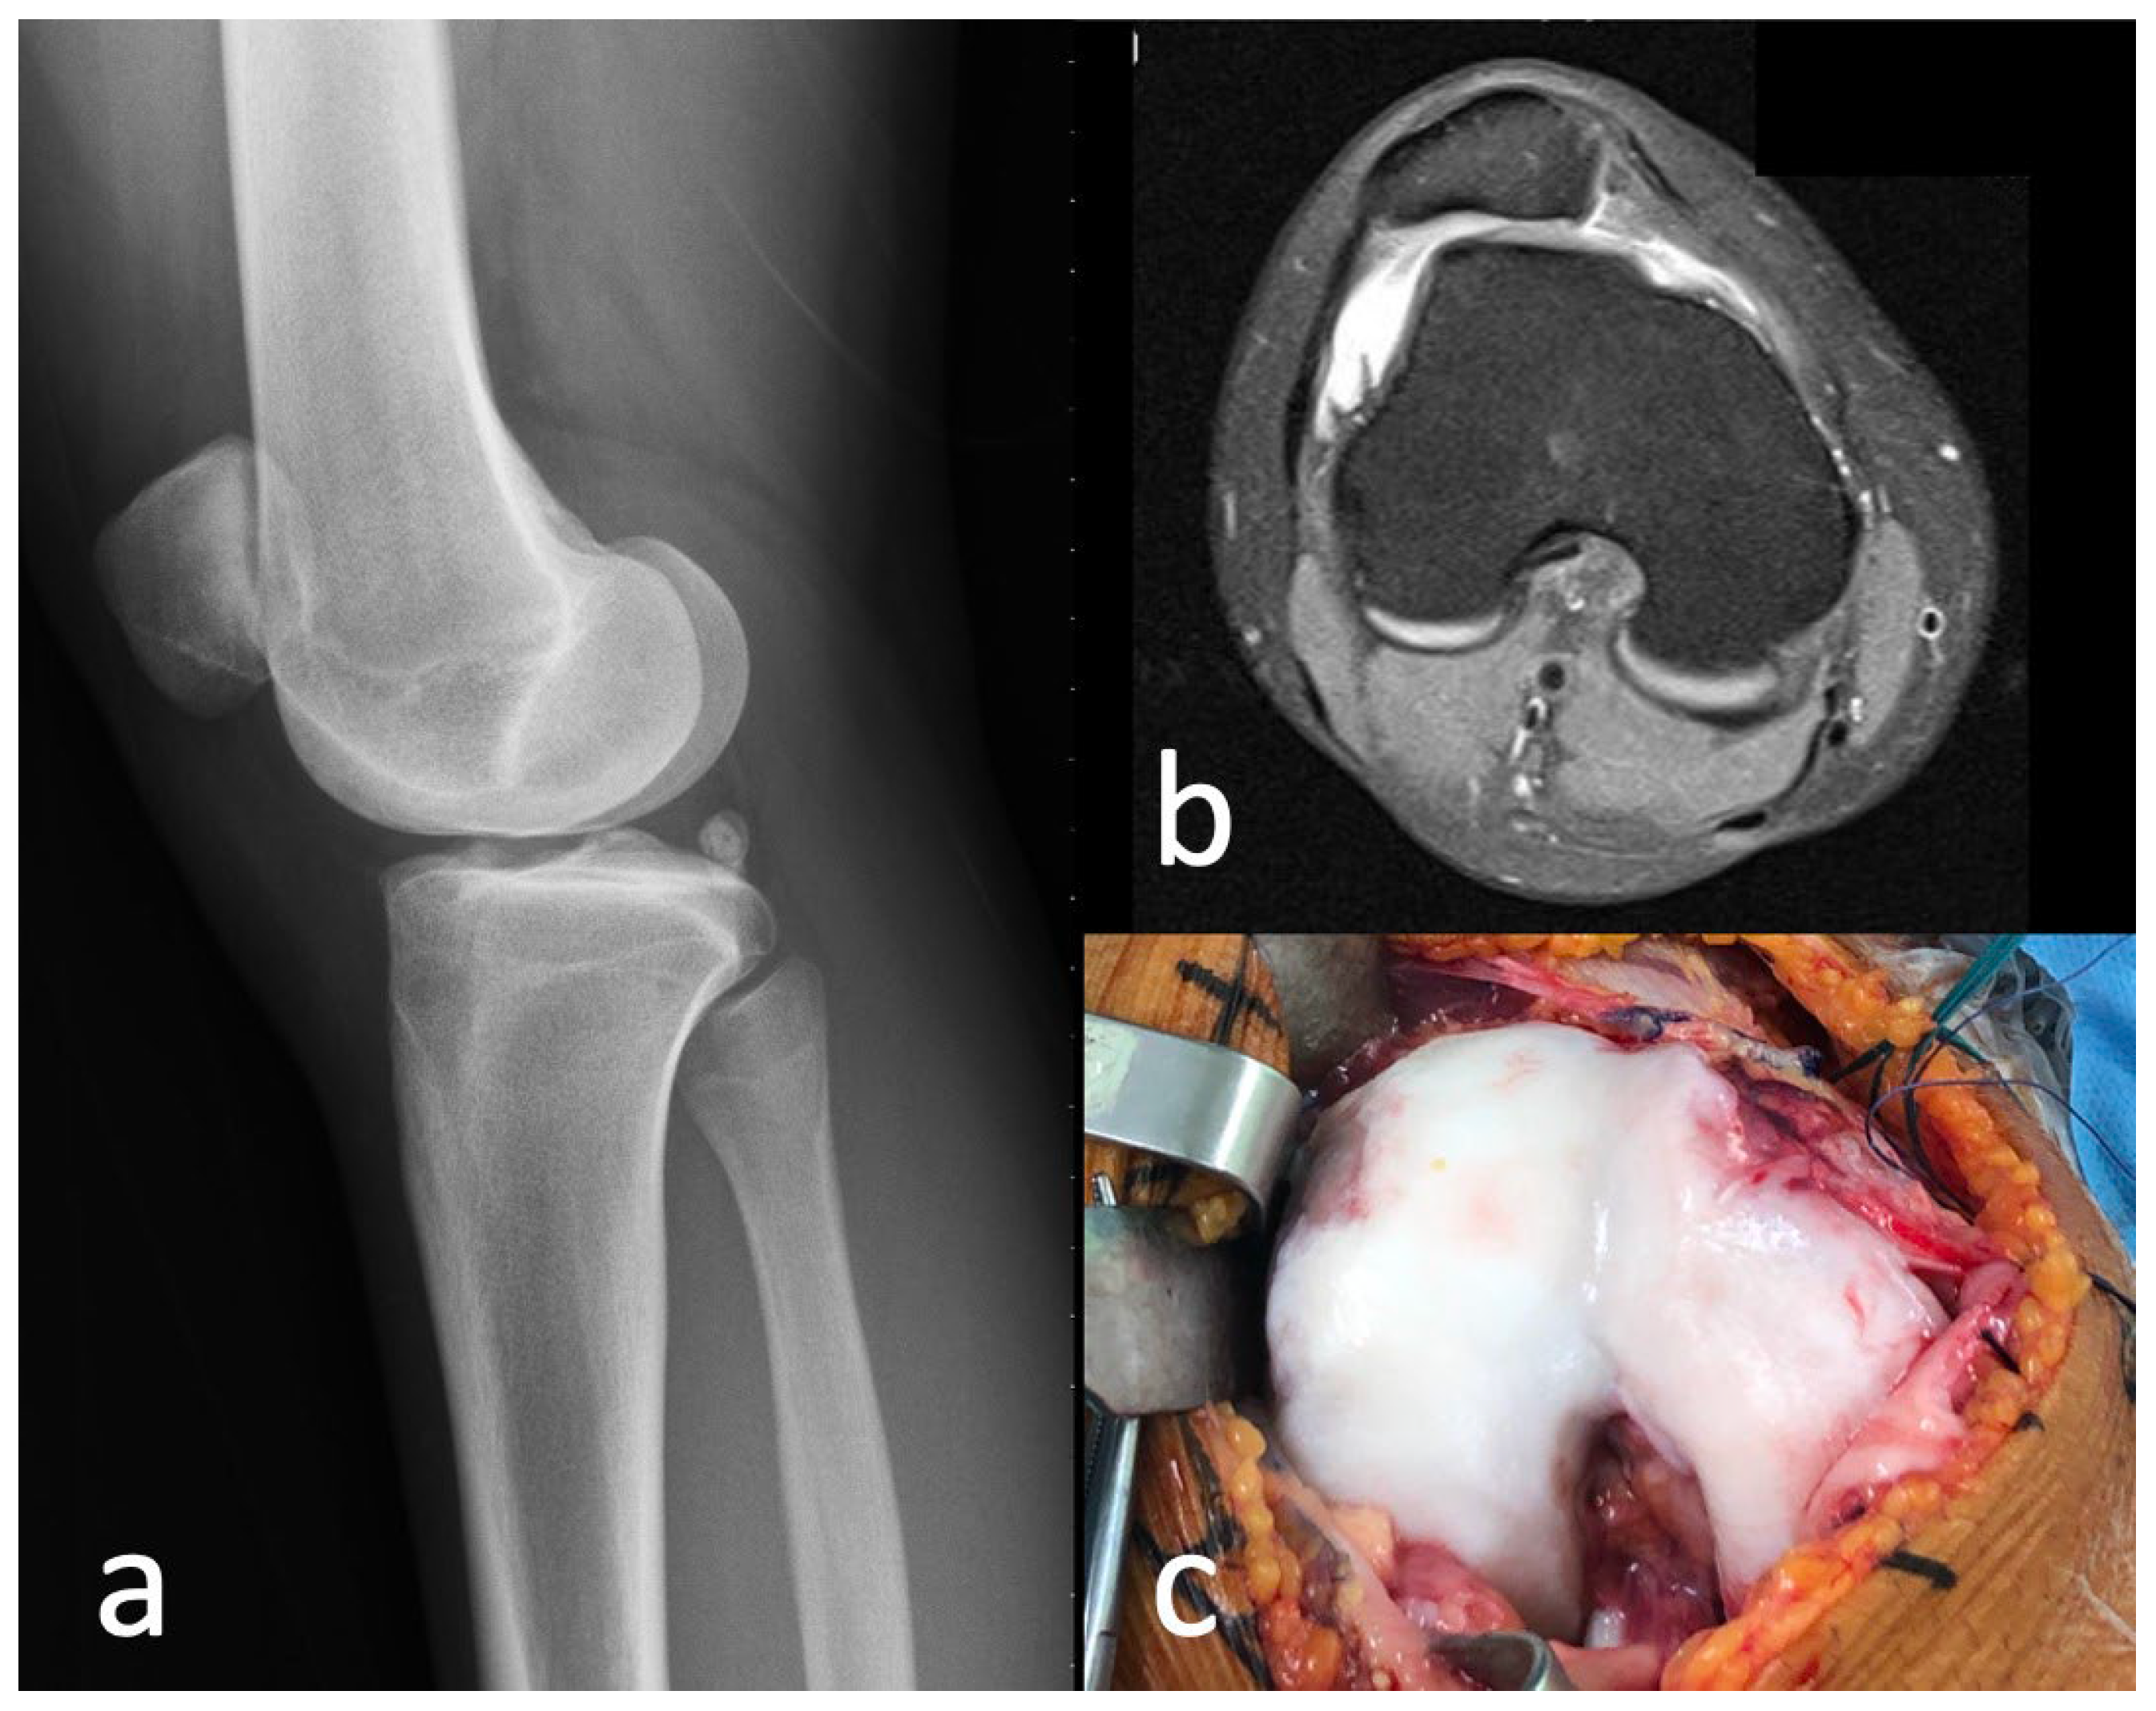

2.1. Case

2.2. Surgical Procedure

3.1. Trochlea Dysplasia